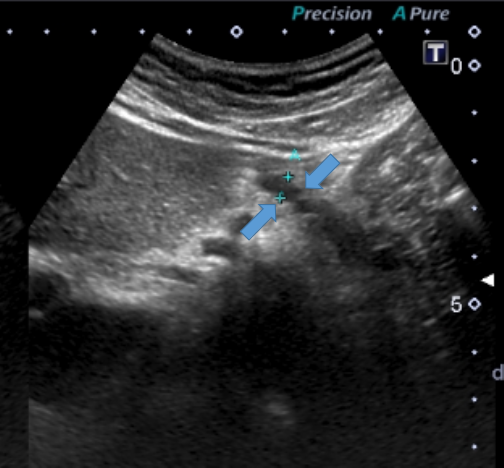

■実際のエコー画像②■

膵臓に18㎜大の巨大な膵石(赤点線部)を認めました。慢性膵炎を考える所見です。